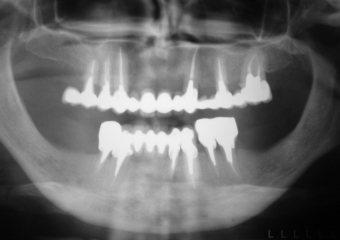

Imagem inicial em 2003 - Clínica Cliniface

Imagem inicial em 2003